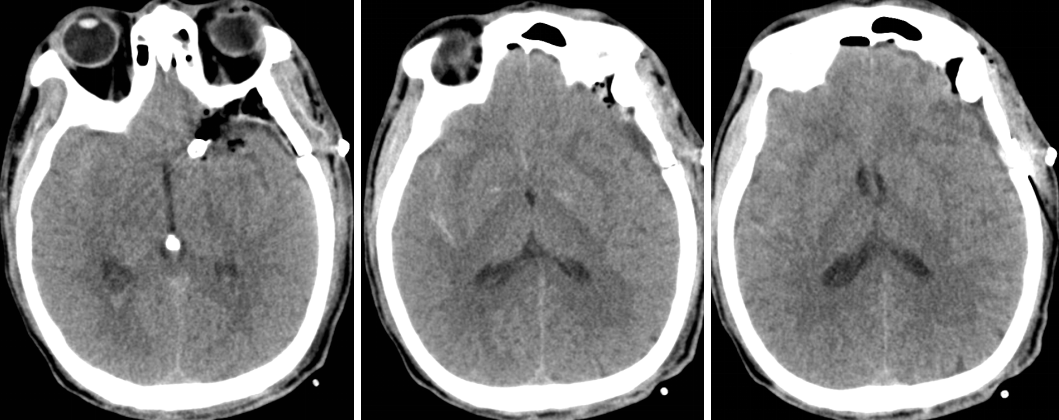

患者约2个月前无明显诱因(否认外伤史)间断出现头痛,头痛为胀痛,左侧较明显,恶心未吐,食欲、睡眠尚可,未予特殊诊治,1个月前患者头痛逐渐加重,思睡,反应略迟钝,行头部CT检查示“慢性硬膜下血肿(双侧)”,于2018年12月15日行颅骨钻孔引流术(左)。术后9天患者恢复良好出院。出院后2周于2019年1月9日患者头痛再次加重,伴有反应迟钝,走路困难,疲乏无力再次就诊,头部CT示“慢性硬膜下血肿(右侧)”,当日再次行颅骨钻孔引流术(右)。术后患者一般状态逐渐好转,无抽搐,无尿便失禁。

术后当日(2019年1月16日)

术后3天(2019年1月18日)